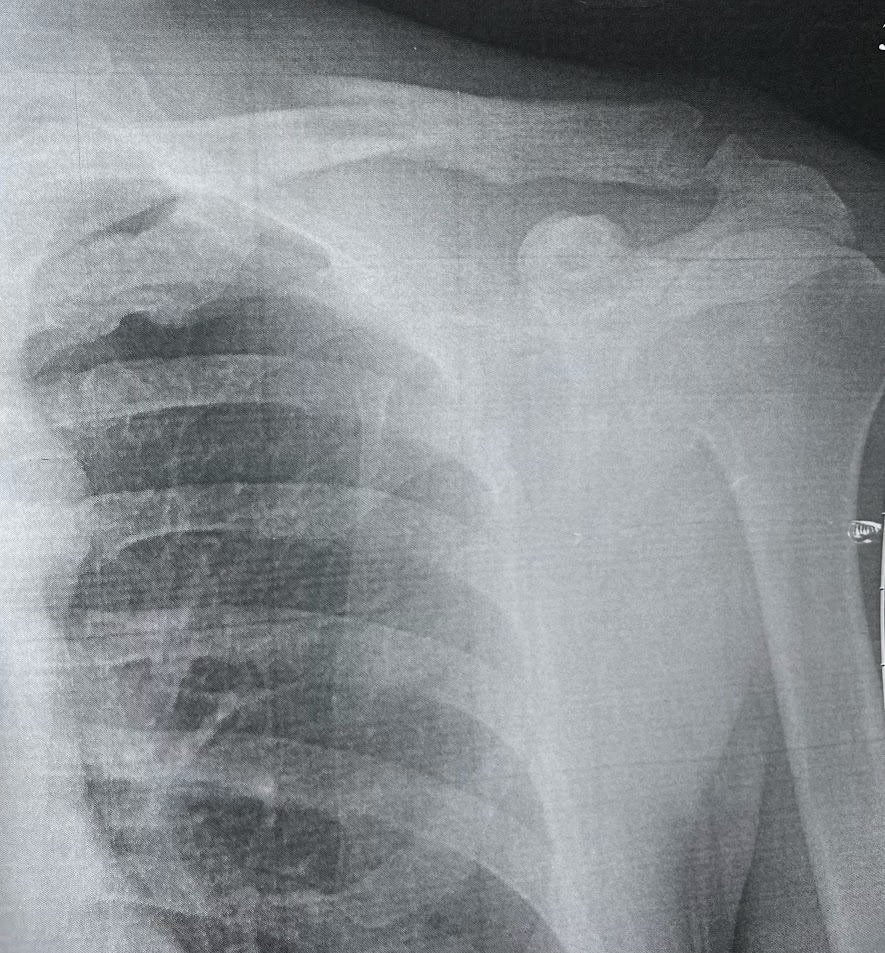

Перелом ключицы